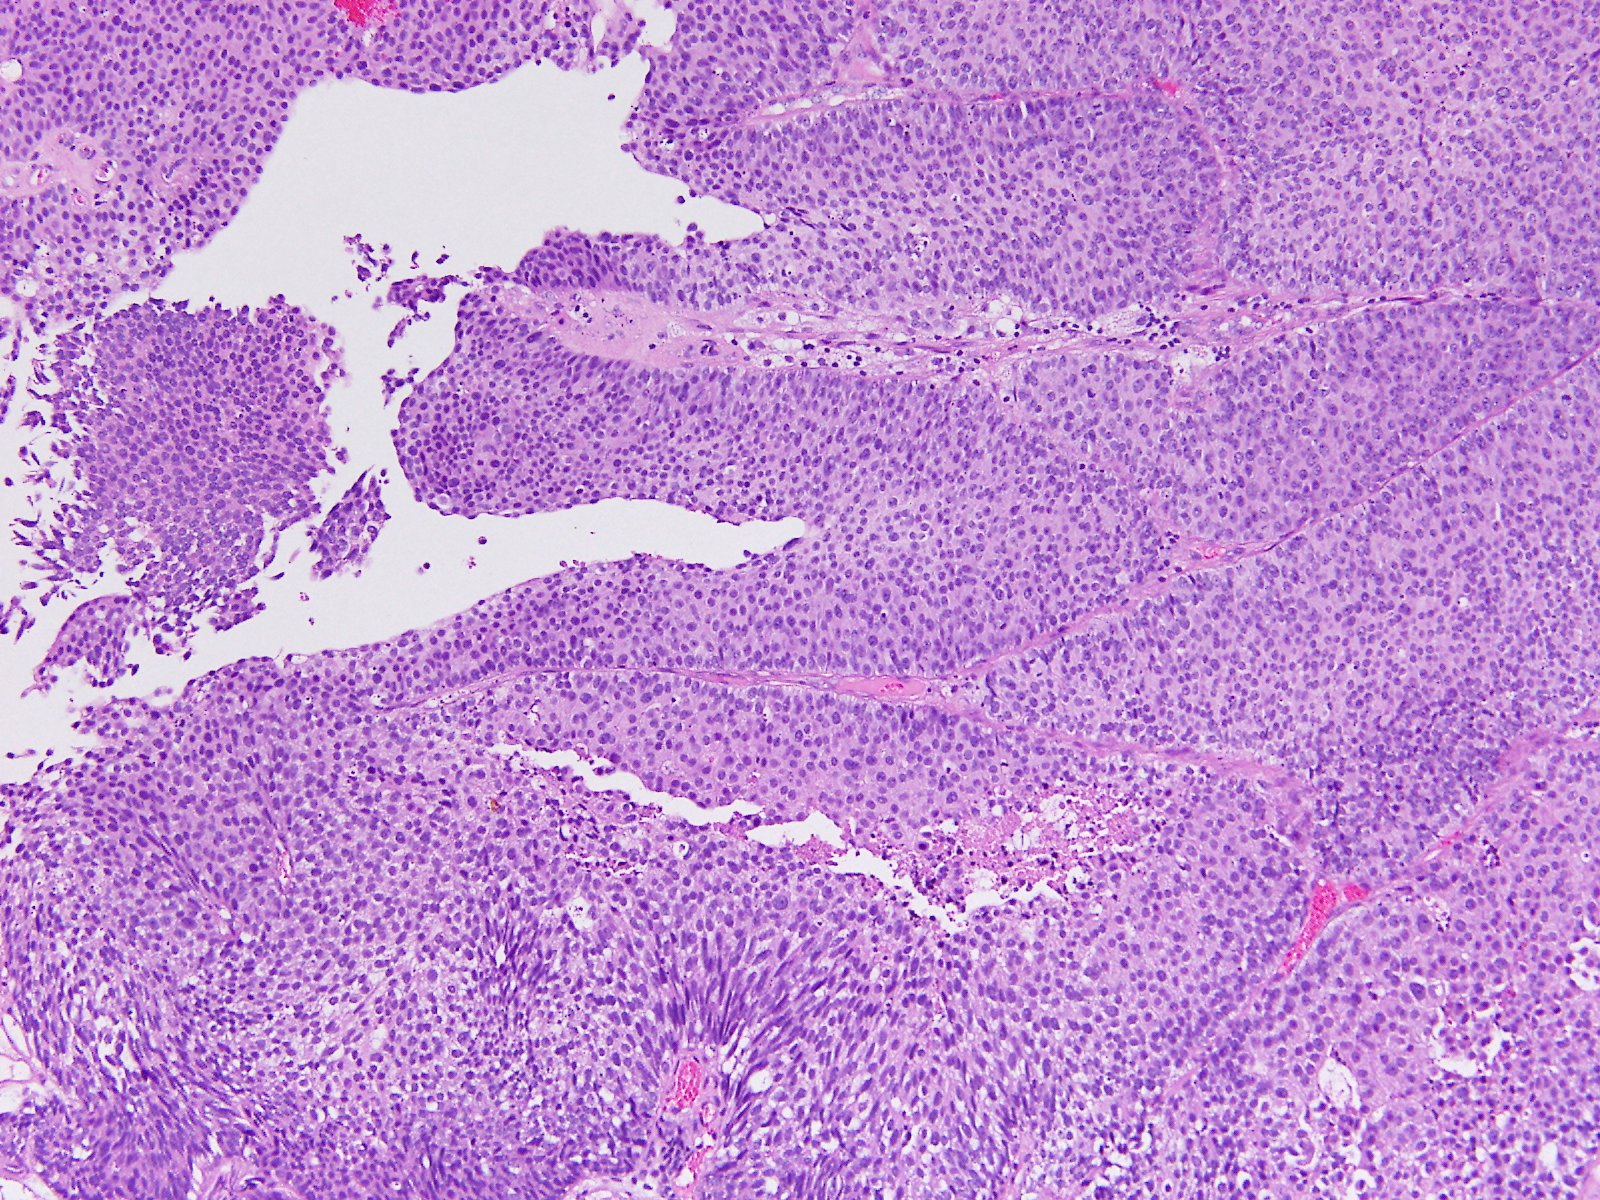

Consensus grade: High-grade papillary urothelial carcinoma (HG-PUC)

Case description (by case creator):

Papillary tumor in TUR-BT.